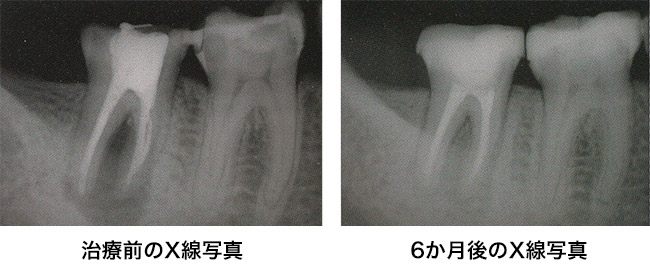

根管治療とは、歯髄を除去する治療です。歯の内部にある「歯髄」と呼ばれる神経や血管を含む組織が、 細菌に感染したり、外傷によって壊死した場合に必要です。 根管治療は、「神経を抜く」とも表現されますが、神経の通っている細かな管をきれいにする繊細な治療であり、歯の基礎を治す重要な治療でもあります。 根管治療の精度により歯の寿命が左右する場合があり、「生涯、自分の歯で食事を楽しんでいただく。」をモットーに治療を行う当院にとって、 豊富知識と経験、培い続けた技術を活かし、美しい治療を心がけています。

虫歯が進行して歯根部分にまで炎症が達してしまうと、根管治療が必要になります。重度になると、炎症は歯根だけでなく、歯を支える骨にも悪影響を及ぼします。自覚症状がない場合もあるため、注意が必要です。

根尖歯周炎(こんせんししゅうえん)とは、細菌の影響が歯を支えている骨の先端部分にまで達している状態です。 その原因には、虫歯の進行、根管治療を以前した部位の再感染、外傷によるダメージがあげられます。